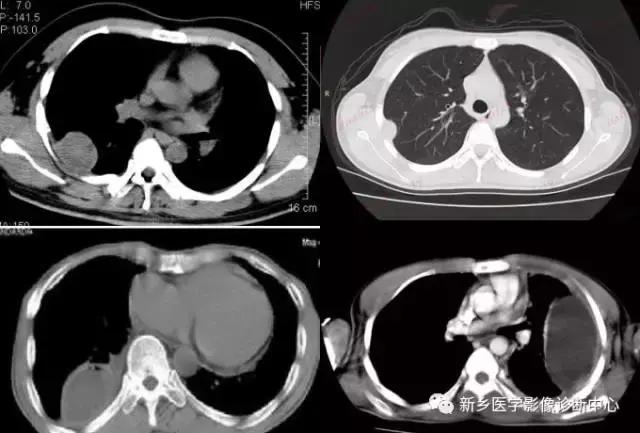

单发肺转移瘤

有原发肿瘤病史,多发于肺下叶。圆形密度增高影,密度常较均匀,边缘清楚,常呈分叶,无毛刺,可见强化。

下为前列腺癌转移:

下为骨肉瘤转移: